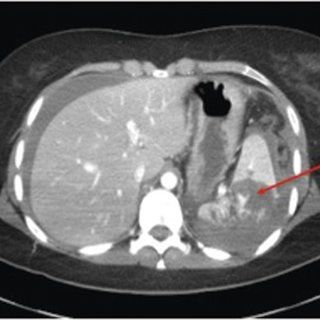

CECT abdomen, traumatic injury

Grade 4 abdomen injury. CECT of abdomen, Traumatic injury Identify the which organs are affected??